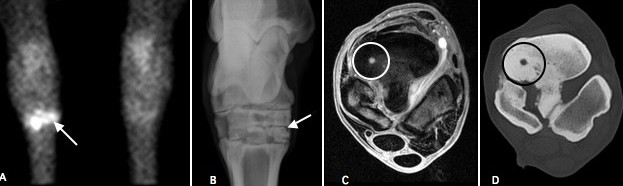

In the above image we have performed a bone scan, radiographs, MRI and CT examination. This is an uncommon example but shows how diagnostic imaging modalities can complement each other. The bone scan on the left shows a bright ‘hot spot’. A radiograph of this site does not show the reason but the MRI and CT scan show a cyst (circled). This case had a screw placed across the cyst.